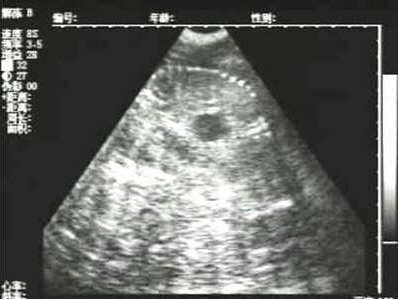

懷孕后期胎兒骨骼圖像

需要注意的是,出現云團狀必須雙側檢查加以確認.根據B超機顯示圖我們大致可以判斷孕齡.圖像呈橢圓或者卵圓形大致為30天左右孕齡;圖像呈橢圓形或者卵圓形外,有明顯發亮骨骼圖像大致為50孕齡左右;圖像囊胚消失,發亮處隱約可見竹節狀東西為成型胎兒骨骼,一般為后期80孕齡以后。一般B超機成像會出現三種顏色,白色、黑色、灰色。白色為密度較高的物體,如骨骼或者結實.黑色一般為液體,包括血液、羊水、組織間隙液體、炎癥病灶等?;疑话銥閷嵸|性物質,如肌肉。